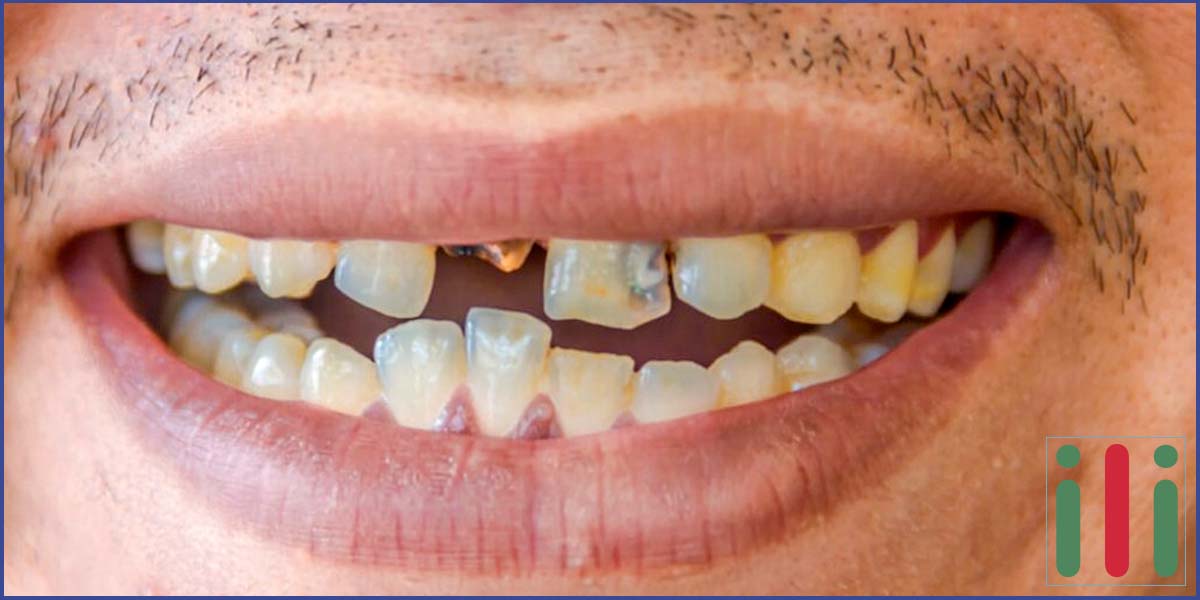

A fog gyökérkezelés egy alapvető fogmentő beavatkozás A konzerváló fogászati ellátás egyik gyakran előforduló „fogmentő” akciója a fog gyökérkezelés. Ez akkor válik szükségessé, amikor megfertőződik és begyullad a foggyökeret alkotó szövet, ami rendkívül érzékeny, miután sűrűn át van szőve idegvégződésekkel. A kezelés célja a gyulladt rész eltávolítása, majd a gyökércsatorna alapos